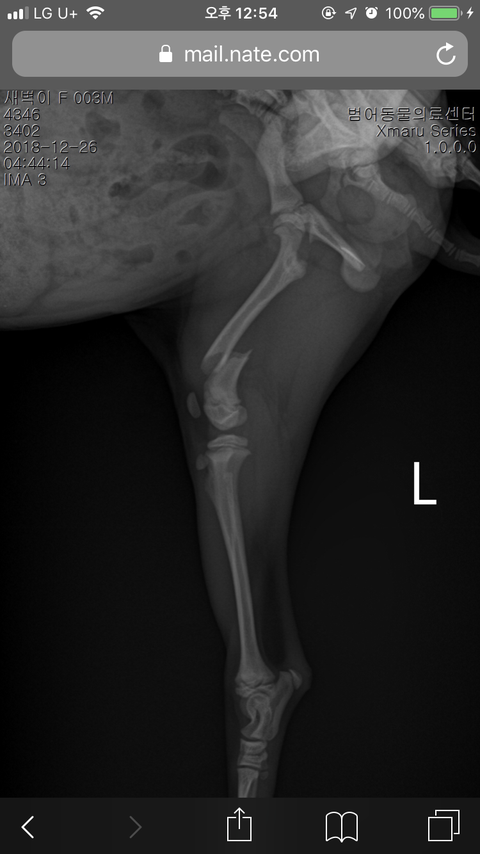

4개월된 1.2키로 포메라니안 여아 골절로 인해 오늘 수술하였습니다. 밤에수술이 가능하다하여 수술을 시작하였습니다 마취가깨면 전화오기로하였습니다 12시경 전화가와서 마취가깨지않는다고 보호자분 오셔야겠다고 하여 급히 달려갔습니다 혈액검사도하였고 제가 너무애기이기도하고 몸무게도 생각보다 덜나가고해서 그럼 수술이 어렵지 않을까요? 라고 하니 사실 저도 고민을많이했는데 마취문제보단 플레이트가 몸에맞을지가 걱정이라면서 전에 비슷한 몸무게도 수술했다고하여 믿고 수술을맡겼습니다 그런데 가보니 이미 혓바닥은 굳어있고 맥박도 제대로 뛰지않고 저희가 만지고나 마사지해주어야 맥박이겨우붙어있었습니다 그런데 의사는 아직 살아있는데 마취가안깨고있는거라고해서 6시간을 기다렸습니다 하지만 애기는깨어나지않고 몸이 차갑더라고요 그래도 의사말믿고 기다렸습니다 그런데 서서히 다리도 굳어가고 똥이 흘러나오더라고요 아 이제 진짜 가는구나 싶어서 그냥 집에델꼬간다하였습니다 병원에서는 의료과실로 애기가 죽은게아니니 병원비반값을 계산하고나왔습니다 집에와서 생각해보니 이상하더라고요 어제까지만해도 잘 뛰어놀던아이가 한순간에 무지개다리 건넜습니다 다른병원에 저나해보니 보호자분을 오라할정도면 이미 상태가 심각한거고 이미 죽어있을확률도 있다고 하였습니다.... 이럴땐 어떡해야하죠 도와주세요 제가 너무 정신이없어서 말을 제대로했는지모르겠네요..긴글읽어주셔서 감사합니다